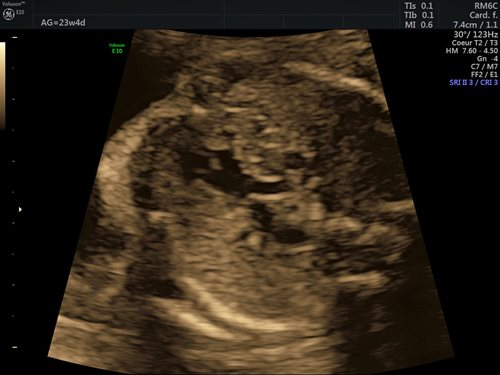

Dans la grande majorité des cas (90 %), l’étiologie des cardiopathies congénitales est multifactorielle, un facteur de risque classique comme des antécédents familiaux au 1er et 2e degré, la présence d’une anomalie chromosomique, d’un diabète maternel de type 1, d’une phénylcétonurie, la prise de certains médicaments ou une infection n’étant pas retrouvé. Pour cette raison, un dépistage systématique par échocardiographie foetale reste indispensable, idéalement entre 18 et 22 semaines de gestation. Le dépistage recommandé consiste en l’obtention d’une vue des 4 cavités cardiaques (fig. 1) et d’une vue des voies d’éjection (fig. 2). (2)

Figures 2